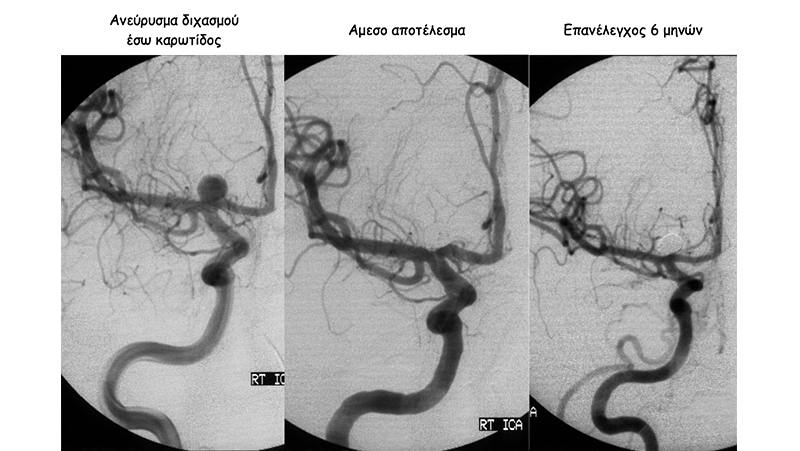

Ραγέν ανεύρυσμα του διχασμού της δεξιάς έσω καρωτίδος με στενό αυχένα (αριστερή εικόνα). Στην μέση, φαίνεται η πλήρης απόφραξη του ανευρύσματος με coils και δεξιά, η σταθερότητα του αποτελέσματος σε αγγειογραφικό επανέλεγχο στους 6 μήνες.